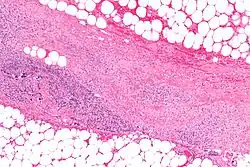

Micrograph of necrotizing fasciitis, showing necrosis (center of image) of the dense connective tissue, i.e. fascia, interposed between fat lobules (top-right and bottom-left of image), H&E stain

Early diagnosis is difficult, as the disease often first appears like a simple superficial skin infection.[4] While a number of labs and imaging can raise the suspicion for necrotizing fasciitis, none can rule it out.[14] The gold standard for diagnosis is a surgical exploration and subsequent tissue biopsy. When in doubt, a 2-cm incision can be made into the affected tissue under local anesthesia.[2][15] If a finger easily separates the tissue along the fascia, then the finger test is positive. This confirms the diagnosis, and an extensive debridement should be performed.[2][15]